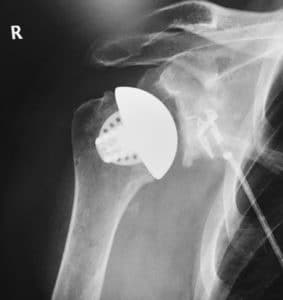

Equinoxe Stemless Shoulder è una protesi a conservazione ossea progettata per l’artroplastica totale anatomica della spalla. La struttura porosa stampata in 3D è progettata per la fissazione biologica, e il fittone è progettata per promuovere la ricrescita ossea

Protesi di spalla Stemless Equinoxe